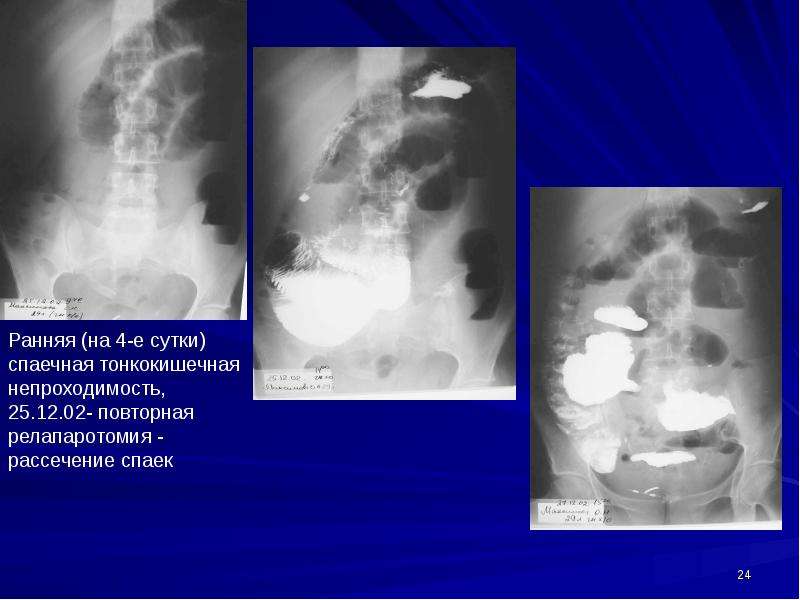

Иллюстрации и информация о симптомах острого кишечного непроходимости

Раздел: Кадры-советчики